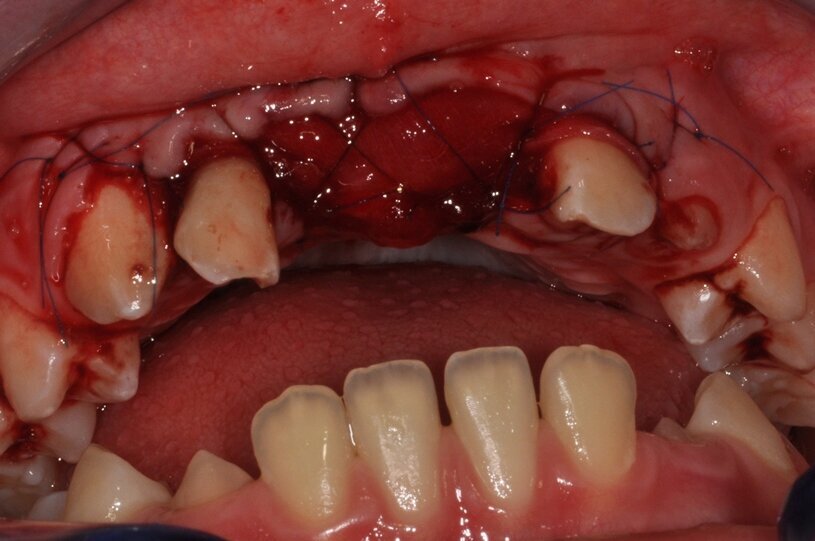

W dniu wizyty w poradni brak było oznak ostrego stanu zapalnego w okolicy 12-11. Widoczne były recesje dziąsła o wysokości 2 mm po stronie wargowej na zębach siecznych górnych przyśrodkowych, zmniejszona wysokość dziąsła zrogowaciałego do wartości 2 mm, spłycony przedsionek (Ryc. 1). Zęby były tkliwe na opukiwanie pionowe i poziome oraz wykazywały I stopień rozchwiania wg Entina. W przekrojach TK widoczny był rozległy przewlekły stan zapalny wokół wierzchołków korzeni zębów 11 i 21 (Ryc. 2), brak blaszki przedsionkowej wyrostka zębodołowego szczęki oraz resorpcja korzeni. Po wnikliwej analizie stanu miejscowego i rozmowie z rodzicami zadecydowano o ekstrakcji zębów 11 i 21 oraz w drugim etapie, ze względu na rozległy i zaawansowany proces zapalny, o autotransplantacji zawiązków 35 i 45.

Ryc. 1_Stan miejscowy przed ekstrakcja zębów 11 i 21.